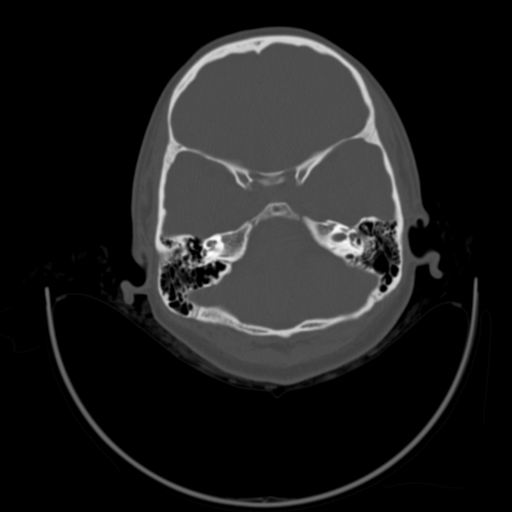

以下是引用随光逐影在2009-3-14 7:58:00的发言:[br]双耳——颞骨ct轴位平扫未见明确异常。